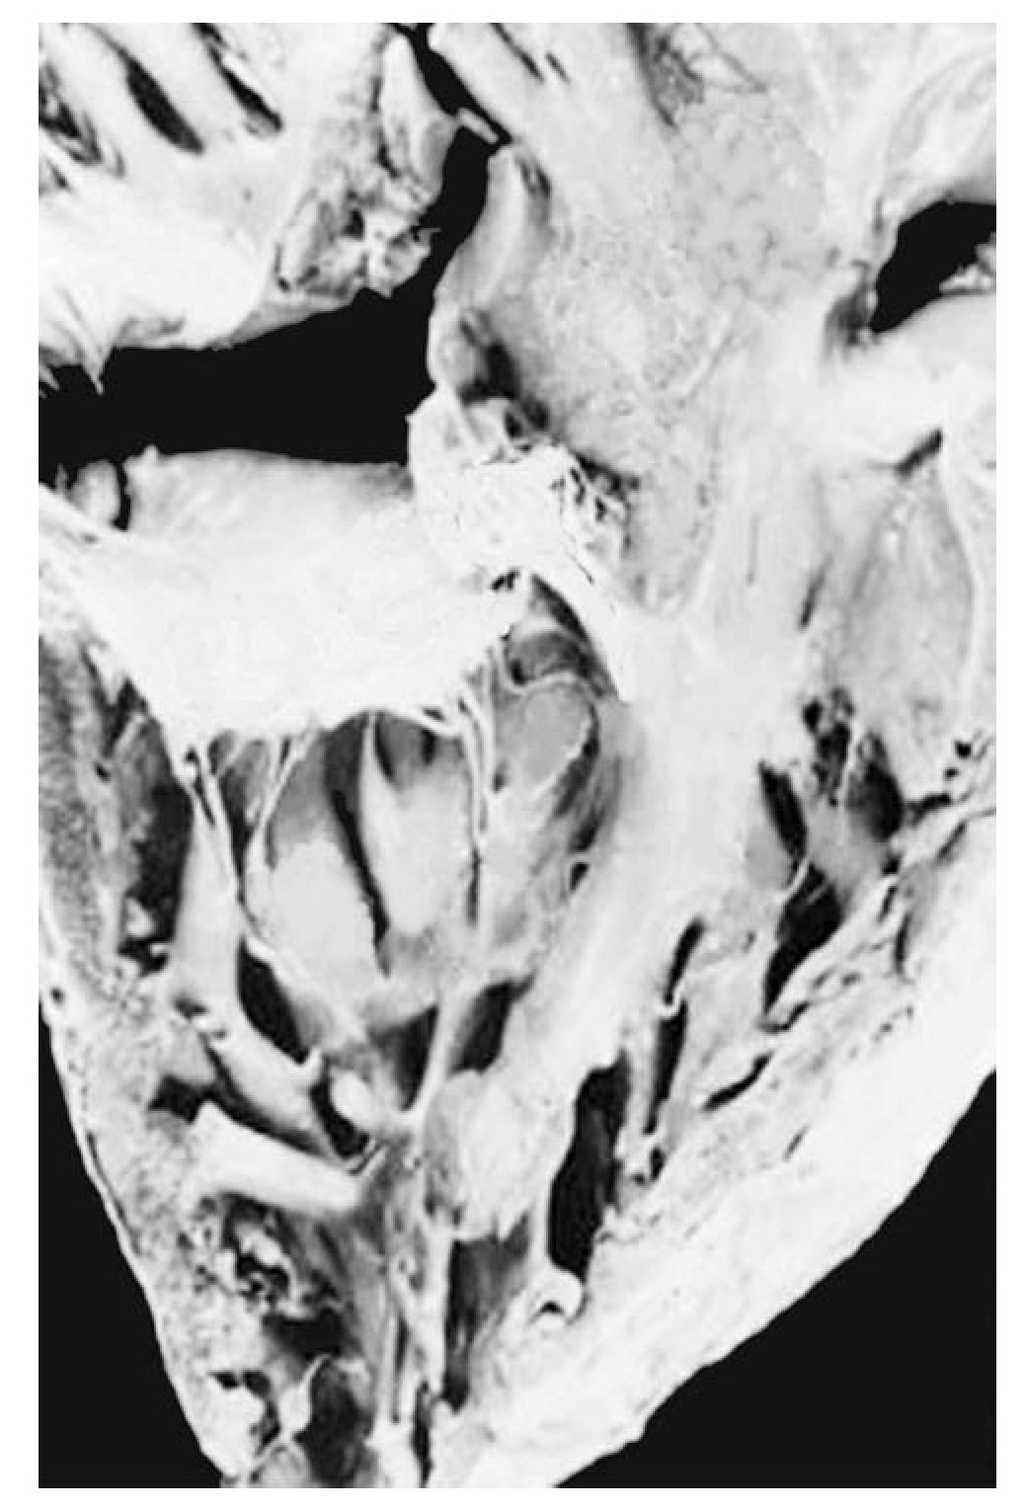

Atrio-ventricular connection: Ventricles are recognized by the trabecular septum's anatomic features. The right ventricle (Figure 3) has a trabecular septum with very thick muscular bands and it also has a structure, the moderator band, inserted in the interventricular septum and in the free wall of the right ventricle, whereas the left ventricle has a trabecular septum with very thin muscular bands in the apical section and it is smooth in the upper section (Figure 4). The former has a group of papillary muscles inserted in the free wall, and the latter has two groups of papillary muscles which are also inserted in the free ventricular wall. Trabecules provide a cavernous-type inner morphological appearance to the right ventricle, whereas the left ventricle has an areolar appearance.

Figure 3. Internal morphology of the right ventricle.